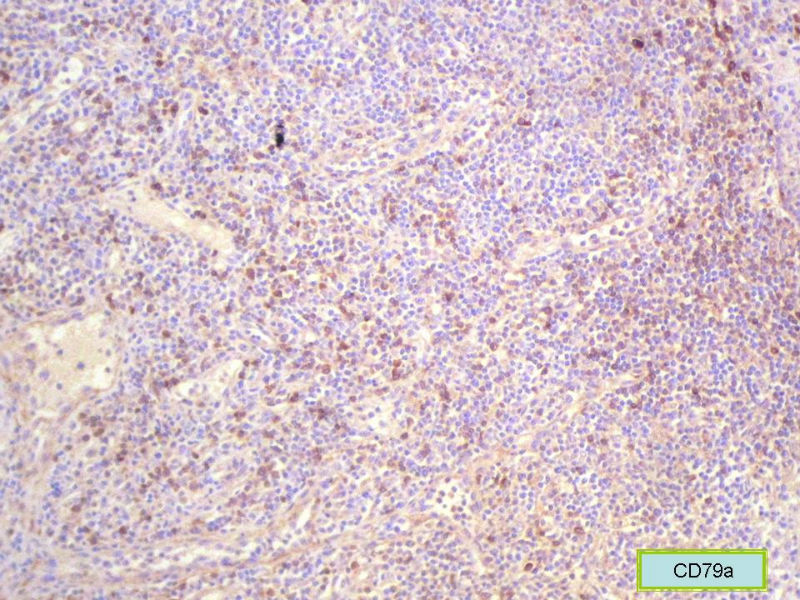

该患者可能存在病毒的感染,抑或是EB病毒的感染,包括CD30+的细胞在内,夹杂在组织细胞、小淋巴细胞之间的一些个大细胞是活化的淋巴细胞,表型看来属B细胞。整个形态呈反应性增生的形态。

标记CD68和溶酶体酶,可能显示组织细胞比较多。

总之,现有的图片显示的形态和IHC标记尚不足以诊断为淋巴瘤,除非有有基因重排的支持。